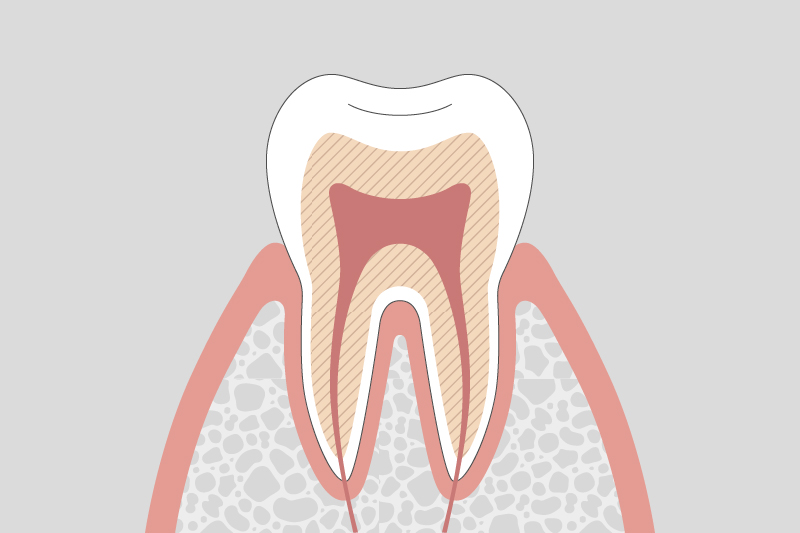

C1.

初期虫歯

エナメル質が溶け始め、白く濁る。